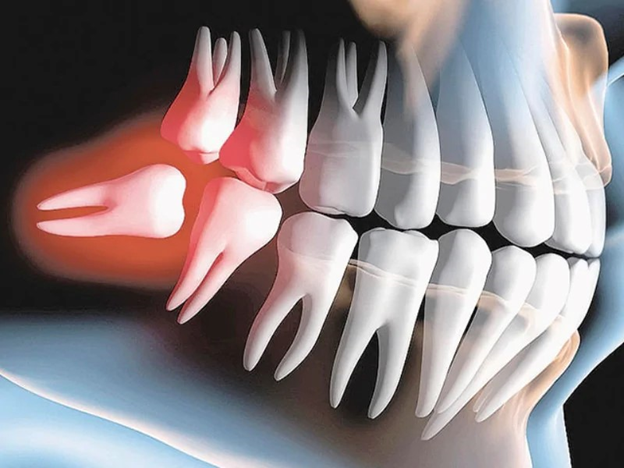

- Răng khôn mọc ngầm

- Toàn bộ răng nằm trong xương hàm, có thể đâm ngang hoặc chèn vào răng số 7 bên cạnh.

- Tại YEN DENTAL, khách hàng sẽ được chụp phim CT Cone Beam 3D để xác định chính xác vị trí và kế hoạch nhổ răng an toàn.